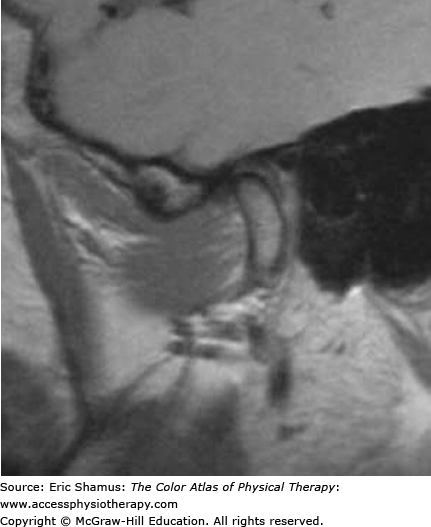

Temporomandibular Joint Disorder

Scenario: A 32-year-old female presents at the clinic with right lateral jaw pain. The patient states she thought she had an ear infection, but the family physician stated the ear was clear. She states she has been under a lot of stress. Her husband states she grinds her teeth at night. Patient has complaints of headaches and difficulty eating apples that are uncut. Upon opening of her jaw, it is noted that the mandible deviates to the left.

Answer with rationale: b. sinus infection, trigeminal neuralgia, Bell’s Palsy. TMJ disorders and sinus infection have pain in similar areas of the head and face. They are differentiated by cause: TMJ disorders are often painful due to muscle aches, whereas sinus pain is due to congestion and swelling. TMJ disorders and trigeminal neuralgia can both cause facial pain and spasm. TMJ facial pain is often caused by diclocation of the joint disc or facial muscles, whereas pain from trigeminal neuralgia is caused by irritation of the trigeminal or 5th cranial nerve. TMJ disorders and Bell’s Palsy often have unilateral pain, discomfort and weakness in common. They are differentiated by cause: TMJ disorders are often muscular or arthrokinematic in origin, whereas Bell’s Palsy is neurological.